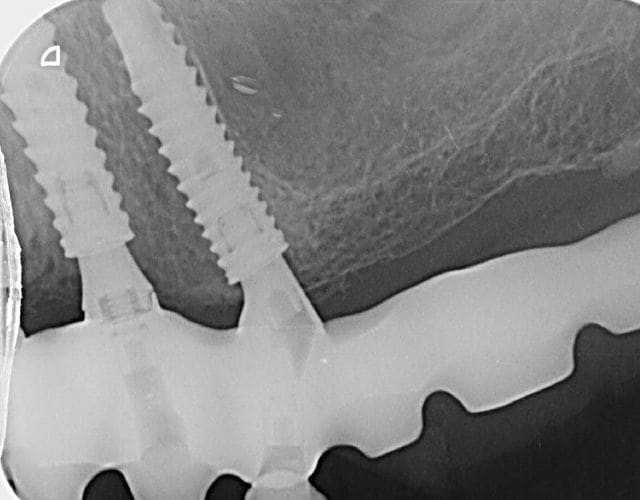

Voici la rétro, un peu déformé désolé.

La deuxième capture est un de mes cas avec des anthogyr axiom reg, ça ressemble, non?

oui, là on y voit clair...et c'est bien des axiom reg....

comme quoi tu vois, une pano, c'est vraiment pas l'idéal pour une identification...